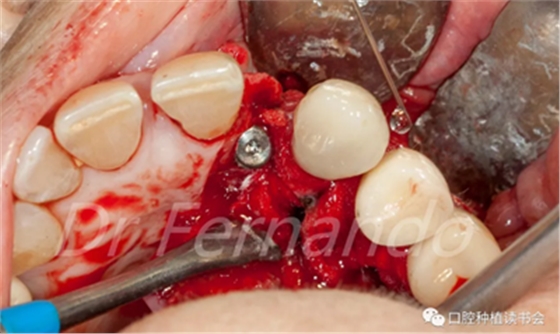

然后根據(jù)種植體周圍炎的標(biāo)準治療程序,先使用磷酸&氯己定凝膠處理種植體表面2分鐘后,接著使用抗生素溶液(透明質(zhì)酸鈉哌拉西林他唑巴坦)處理5分鐘,然后使用Cerasorb ?M 骨粉植骨(Curasan?-科盧森)(圖 21)。

圖21 機械&化學(xué)凈化種植體表面后,使用Cerasorb ?M 骨粉植骨